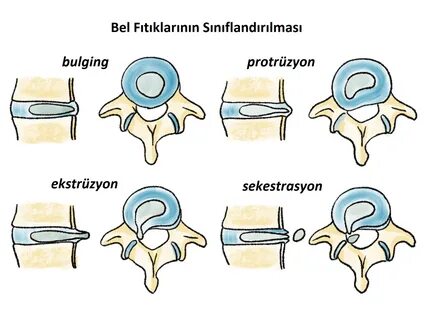

Bel fıtığı hakkında doğru sanılan 10 yanlış!

Bel ağrıları, yetişkin popülasyonda hekimlere en sık başvuru nedeni olarak ilk sırada yer alıyor. Toplumumuzda her 10 kişiden 8’i yaşamlarının herhangi bir döneminde bel ağrısı sorunuyla karşılaşıyor. Yaygın inanışın aksine, bel ağrılarının çok az bir kısmı ‘fıtık’ nedenli oluyor. Beyin ve Sinir Cerrahisi Uzmanı Prof. Dr. Ziya Akar, toplumda bel fıtığı hakkında doğru sanılan hatalı bilgileri anlattı; önemli öneriler ve uyarılarda bulundu.